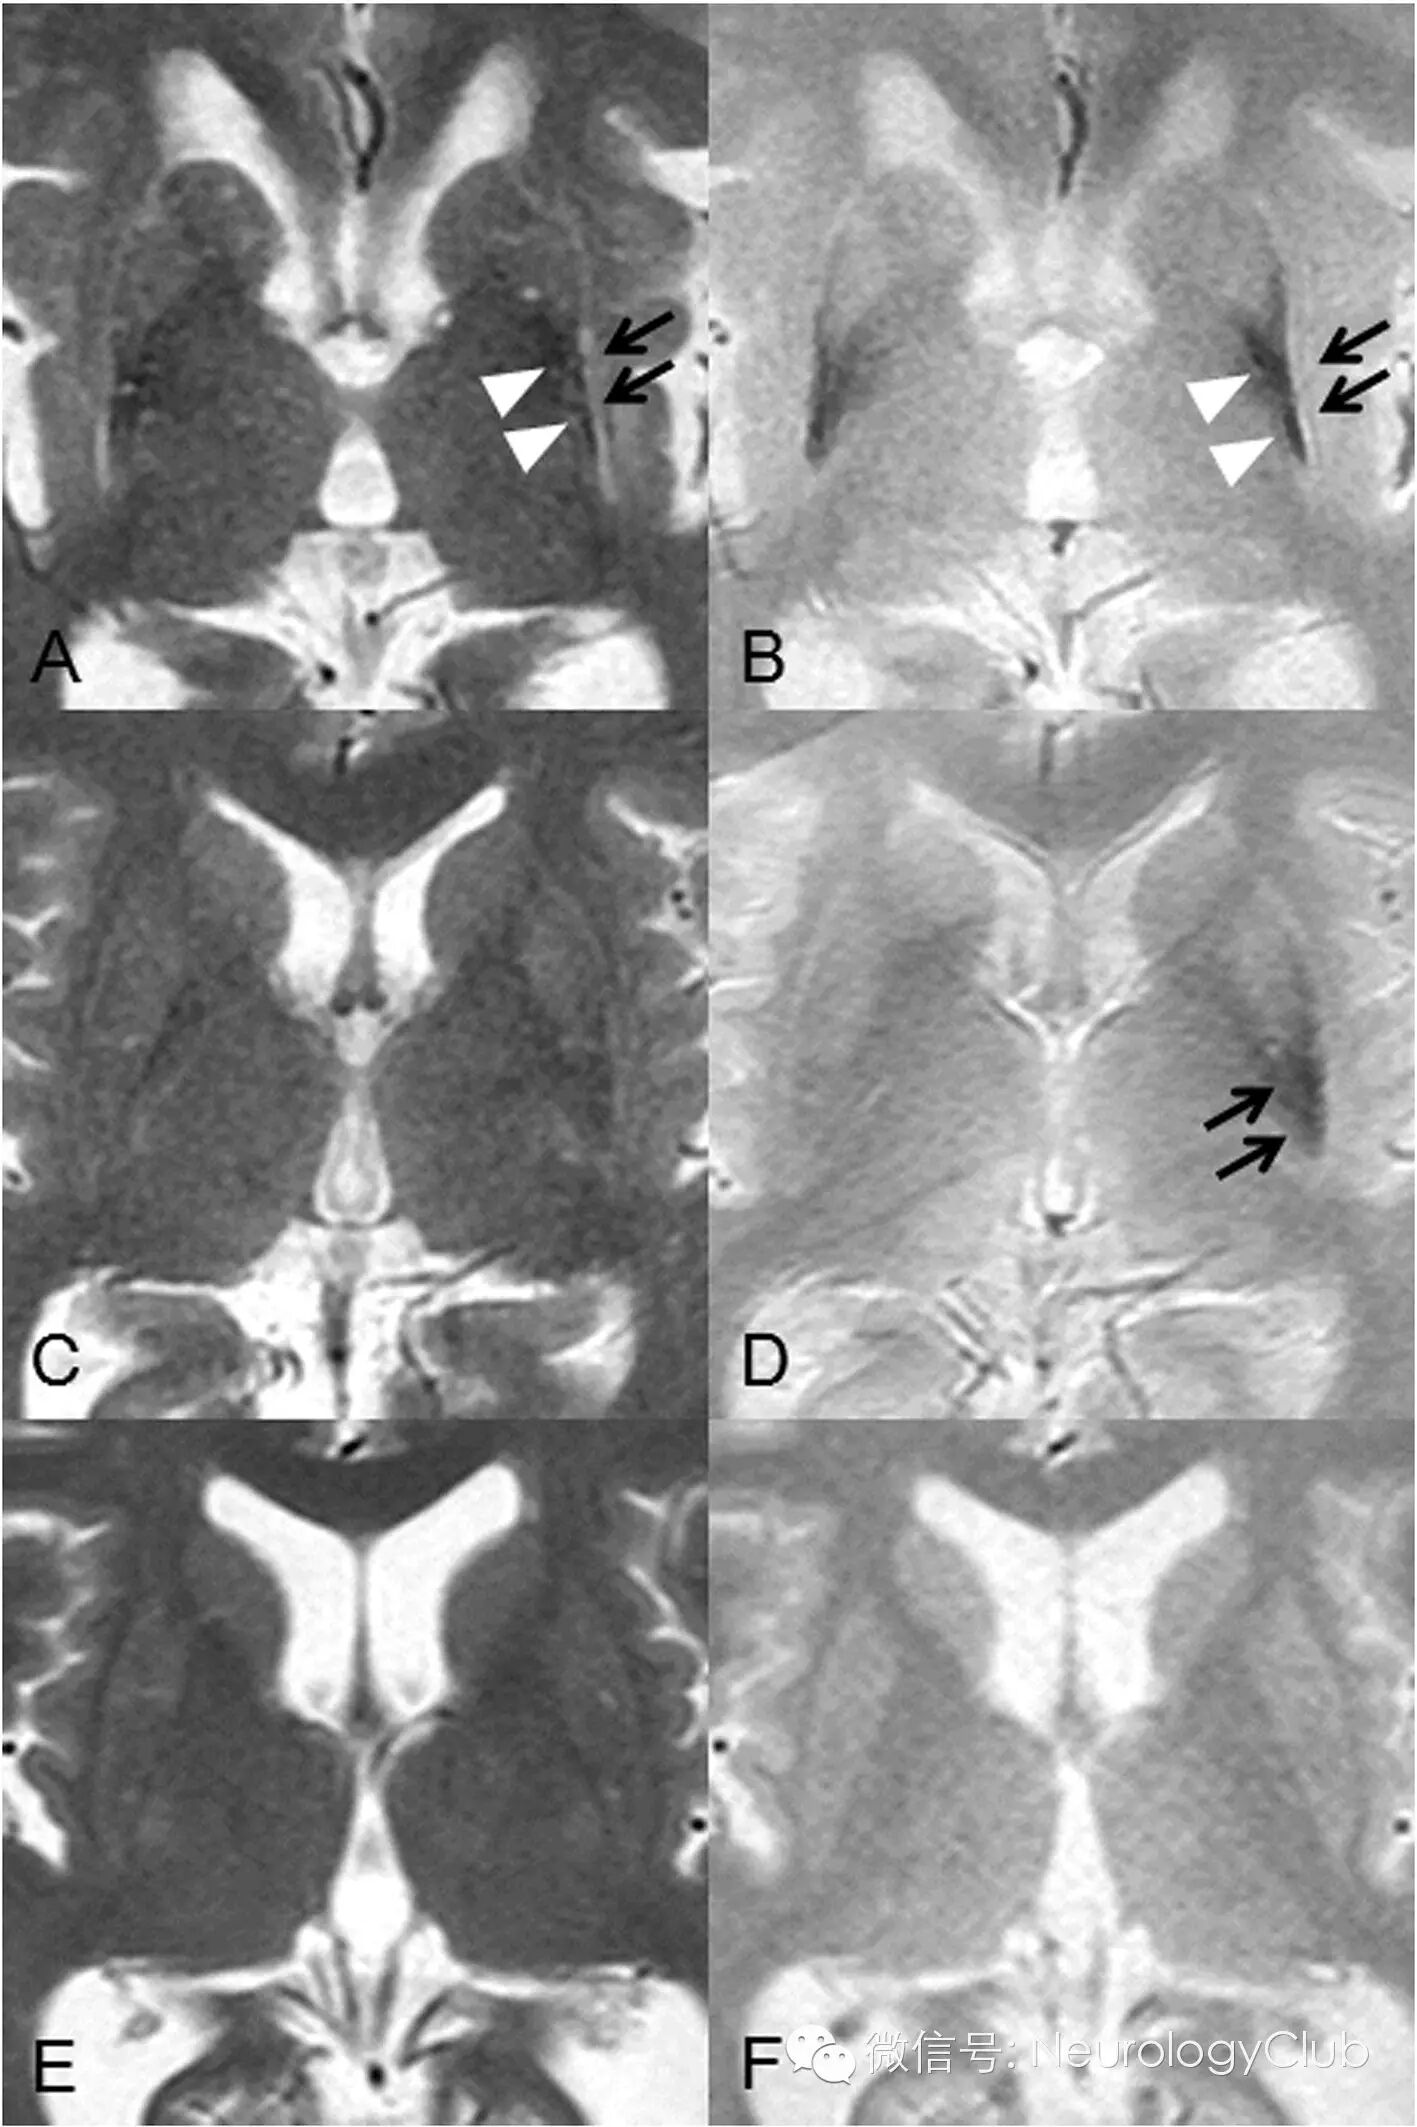

T2*WI诊断MSA的敏感度高于T2WI

近来的研究表明,梯度回波序列(T2*WI)比T2WI在发现MSA“十字征”和壳核改变上更为敏感。临床上怀疑MSA而普通MRI正常的患者,必要时可进一步行T2*WI检查。

72岁女性,诊断为MSA-C。a,c为最初的MRI;b,d为1年后复查的MRI。a-b:T2-WI;c-d:T2*WI。T2*WI相比T2WI在不同时期能更清晰的显示“十字征”

A:MSA-P患者的T2WI上可见壳核外侧缘高信号(黑箭),而壳核内为低信号(白箭头)伴萎缩;B:T2*WI上有类似改变;C:另一MSA-P患者壳核在T2WI上无异常改变;D:同C患者T2*WI上可见壳核后外侧低信号;E-F:健康对照组T2WI和T2*WI上均未见壳核异常信号。